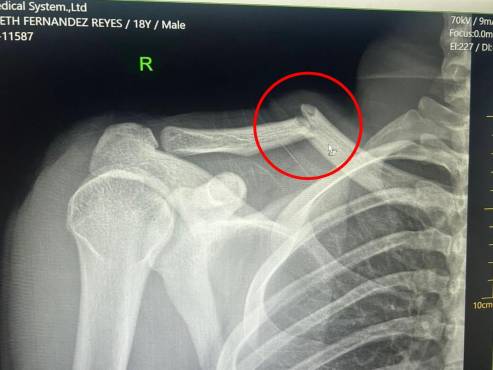

Luego de los estudios realizados, DIEZ conoció que el joven futbolista del conjunto verdolaga sufre una fractura de clavícula en el hombro derecho, producto de un fuerte choque con Elvin Casildo, donde el defensor del Victoria lo frenó con fuerza desmedida.

Los Rayos-X que le realizaron a Jaylor Fernández luego del choque contra Elvin Casildo en el Marathón-Victoria.

El tiempo estimado de recuperación para este tipo de lesión es de entre 10 y 12 semanas, es decir, entre dos y tres meses fuera de las canchas. Esto significa que Fernández prácticamente se perderá lo que resta del torneo Clausura 2026 de la Liga Hondubet.